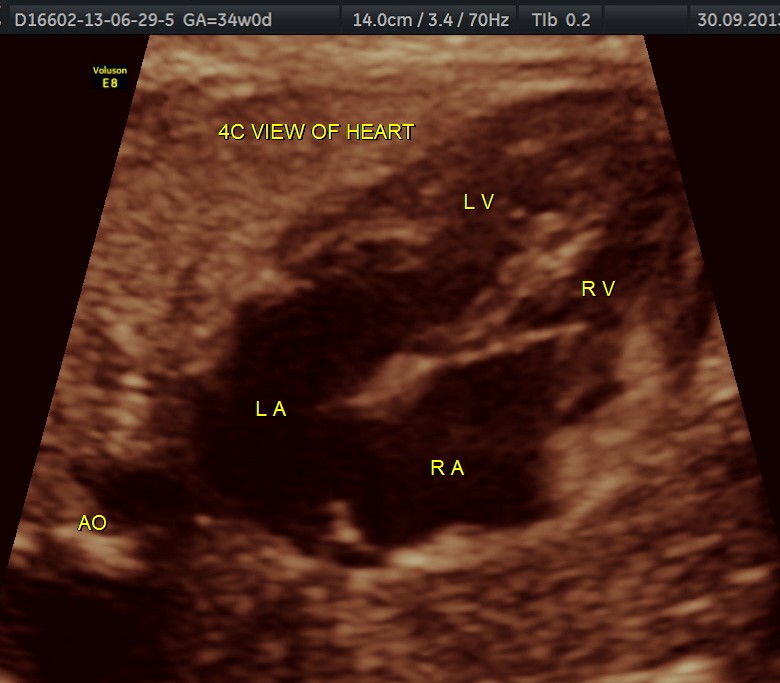

The following are of the 34 weeks gestation :

The 4 chamber view shows the patent foramen ovale. 2 pulmonary veins are also seen entering the left atrium.